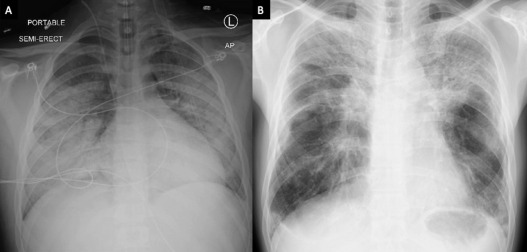

La lesión pulmonar asociada al uso de cigarrillos electrónicos o al vapeo es conocida como EVALI (: E-cigarette, or Vaping, product use Associated Lung Injury). Se trata de una enfermedad grave en la que los pulmones pueden dañarse por las sustancias contenidas en los cigarrillos electrónicos y el vapeo de sus productos.

Una mujer de 19 años acudió a urgencias tras varios días con dificultad para respirar, fiebre y tos productiva. Tenía antecedentes médicos de obesidad y utilizaba diariamente el vapeo durante un año, usando principalmente productos de vapeo de tabaco y ocasionalmente vapeando marihuana. La paciente negó cualquier contacto con piscinas, jacuzzis, fuentes, sistemas de aire acondicionado y no tuvo exposición a aves, otros animales o mohos. En el día 7 de ingreso en cuidados intensivos, la prueba de antígeno de orina dio positivo para Legionella.

Recientemente se ha publicado el caso de un hombre de 32 años sin antecedentes médicos que presentó enfermedad del legionario en el Methodist University Hospital (Memphis, Tennessee, USA), en 2024. Un antígeno de orina de Legionella positivo confirmó el diagnóstico de infección por Legionella pneumophila serogrupo 1. El enfermo se complicó con insuficiencia renal que requirió hemodiálisis y lesión hepática aguda. En la encuesta epidemiológica, el paciente respondió que usaba el vapeo, aunque no hubo ni análisis de detección y, por tanto, confirmación microbiológica de contaminación por Legionella en el dispositivo de vapeo.

En 2023, un hombre de 62 años fue ingresado en Honolulú por neumonía. Los cultivos de especímenes respiratorios y el antígeno en orina fueron positivos para Legionella. Según la publicación, el paciente informó que trabajaba desde casa, realizaba mantenimiento regular de su aire acondicionado (sic) y no había realizado ningún viaje reciente. Tras un nuevo interrogatorio, informó de un historial de uso reciente de productos de vapeo de tabaco, aunque tampoco se realizaron analíticas en el dispositivo del vapeo.